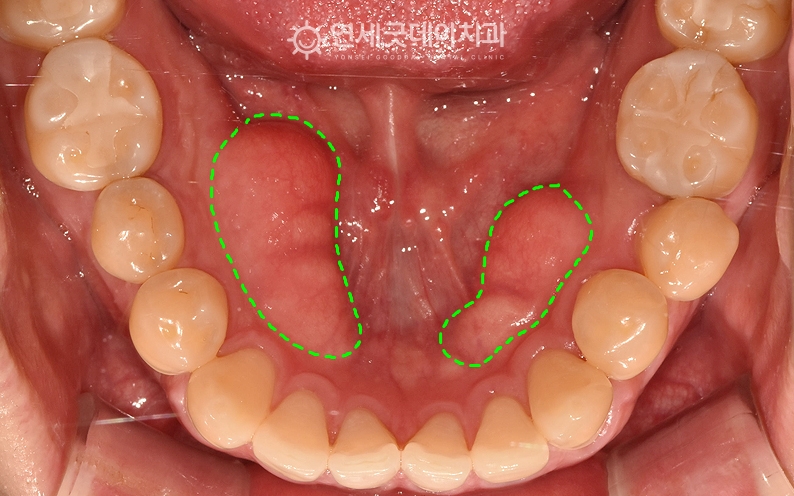

하악 골융기(토러스, torus) 제거, 치조골성형술 치료전후

▲ 치료전 (촬영시기 : 2025년 10월)

환자분은 하악골융기 하방으로 음식물이 많이 끼고

토러스는 씹는 힘에 보상하기 위해 뼈가 자라나는 현상입니다.

환자분은 치조골성형술을 통해

▲ 치조골성형술 직후 (촬영시기 : 2025년 11월)

하악골융기 제거 직후로, 울퉁불퉁한 골융기가 제거되고

10일 후 경과체크를 위해 내원하셨는데요.

▲ 치조골성형술 치료전후 비교 (촬영시기 : 2025.10 ~ 2025. 11)

하악골융기는 자극에 의해 뼈가 자라는 것으로

무조건 토러스를 제거해야 하는 것은 아니지만,